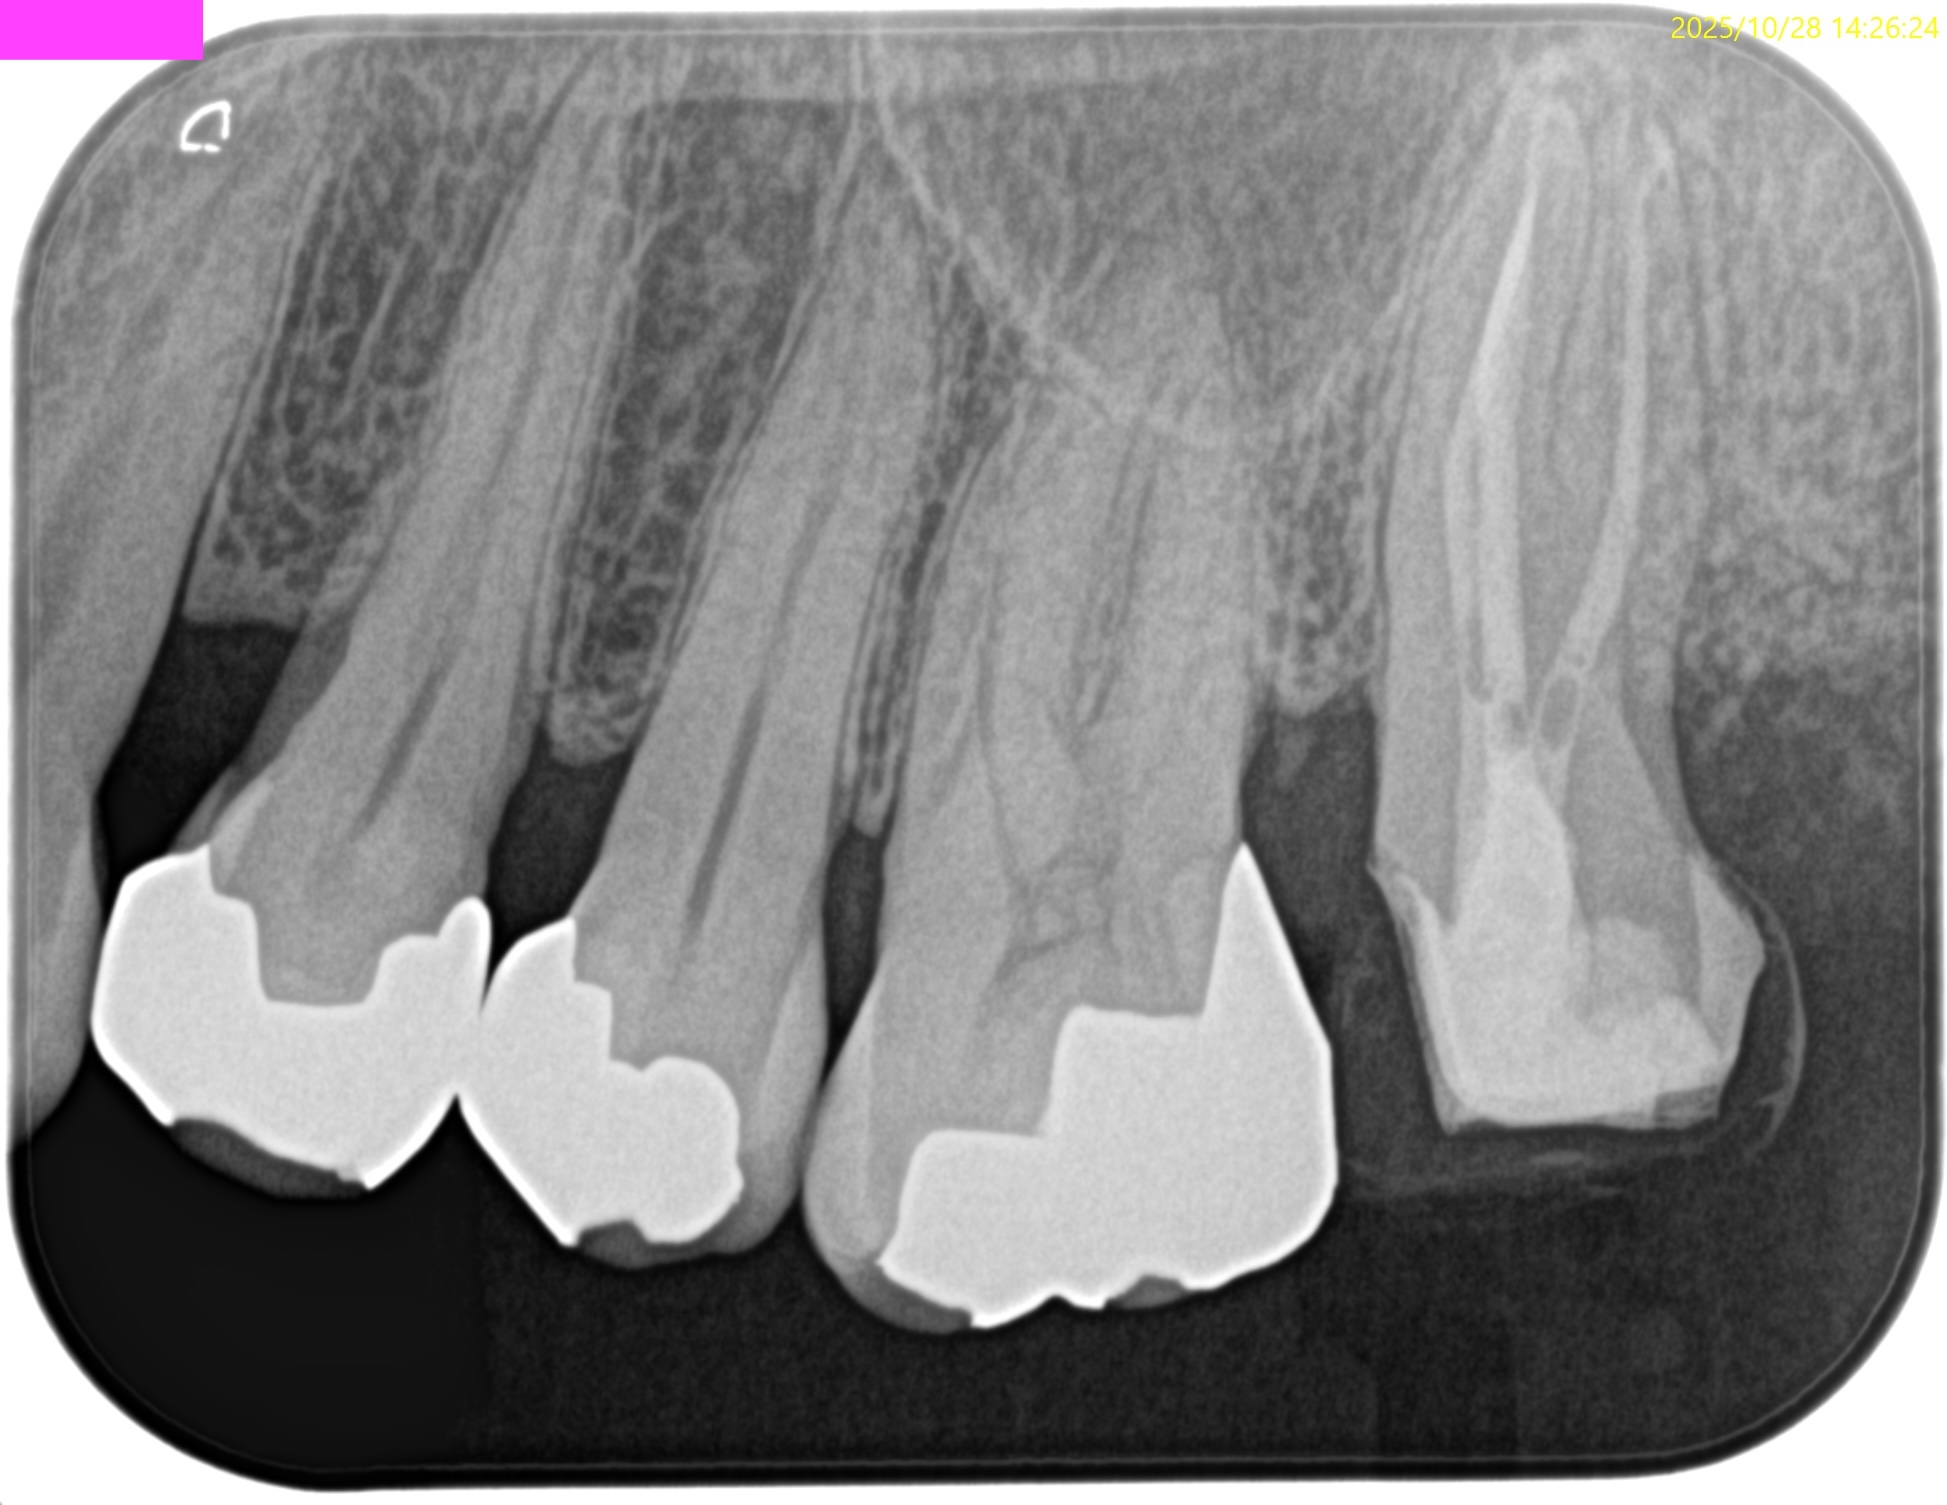

PA(2024.7.31)

CBCT(2024.7.31)

MB

DB

P

根尖病変があり、上顎洞炎を呈している。

根管治療が必要だ。

Pre-op Endo Diagnosis(2024.7.31)

Pulp Dx: Pulp Necrosis

Periapical Dx: Symptomatic apical periodontitis

Recommended Tx: RCT